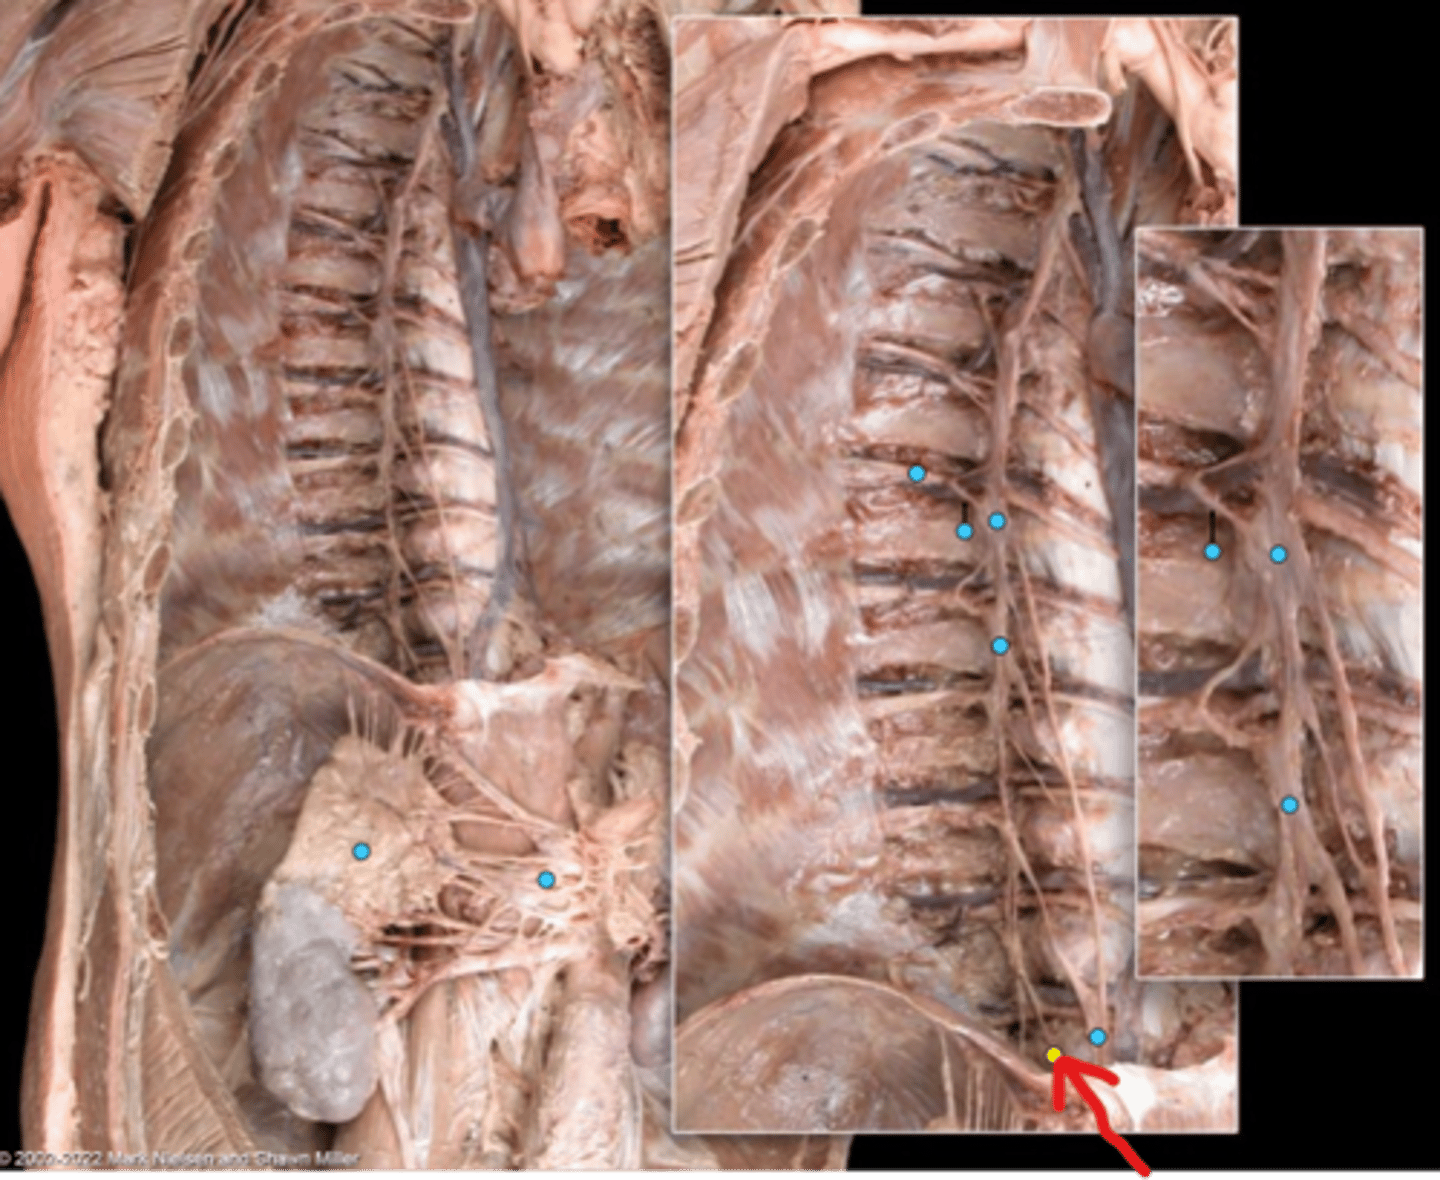

Suprarenal gland

Celiac ganglion

Intercostal nerve

Communicating ramus

Sympathetic trunk ganglion

Sympathetic trunk

Lesser splanchnic nerves

Greater splanchnic nerve

Anterior (ventral) ramus

Spinal nerve trunk

Posterior (dorsal) ramus

Spinal ganglion